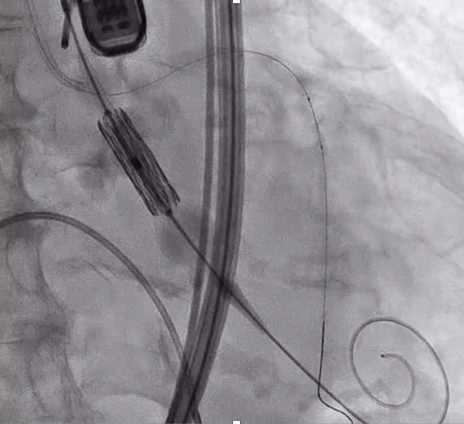

TAVI時の冠動脈閉塞への対策

 冠動脈閉塞は一旦発生すると速やかにそれを解除する必要があります。しかしながら、弁尖についた石灰化の塊が冠動脈入口部を塞いでしまうと、それを一から解除しに行くのは非常に困難です。そのため、リスクが一定以上と考えられる症例においては、冠動脈プロテクションを行なった上で弁の留置を行います。

 弁を留置する前に、事前に冠動脈にガイドワイヤーを通し、多くの場合はバルン(場合によってはステント)を冠動脈内に待機させておきます(写真1)。弁の留置後、冠動脈閉塞が確認されれば、速やかに待機させていたバルン(ステント)を入口部まで引いてきて閉塞の解除を行います(写真2)。 (田中哲人)